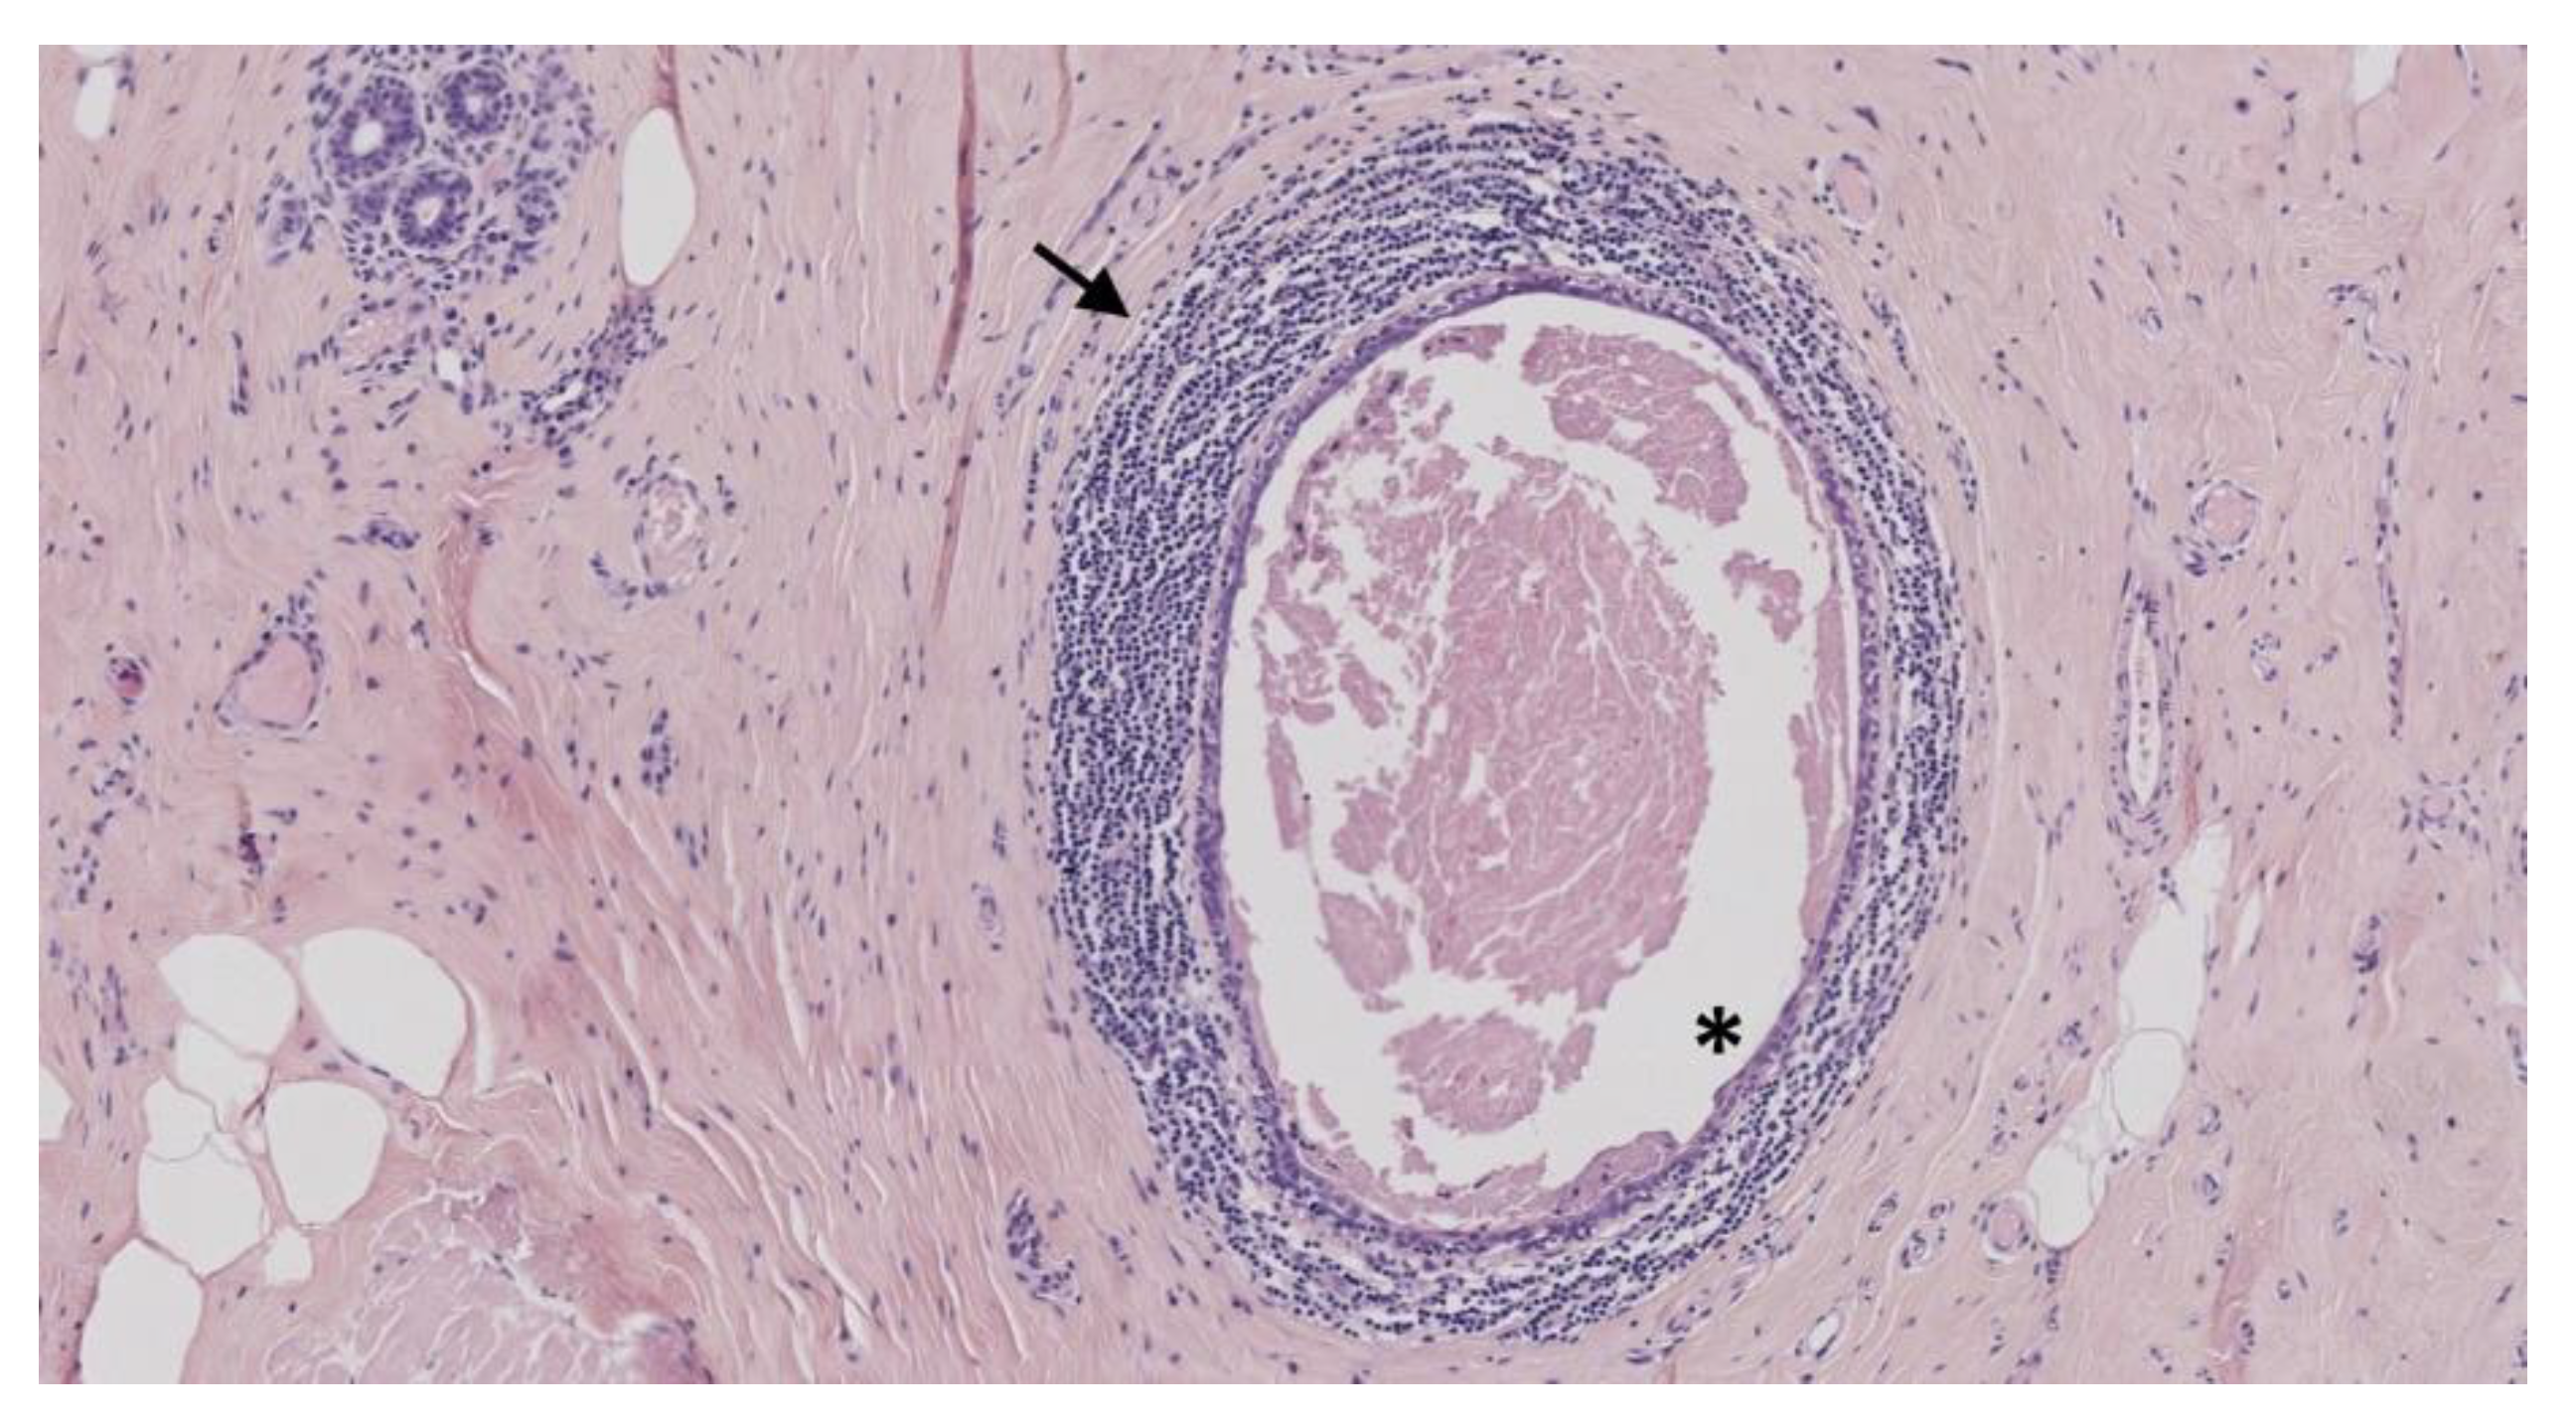

6. Vasculitis

6.1. Polyarteritis Nodosa